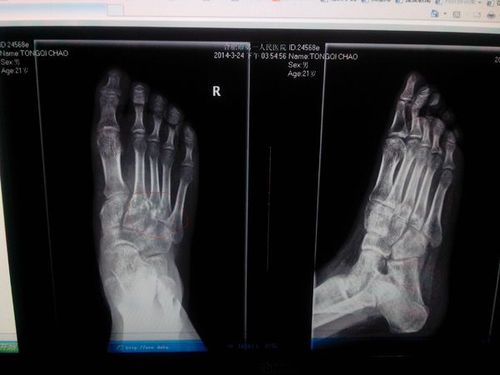

脚ct图片大全骨折,脚踝骨折ct图片清晰

脚踝骨折有ct片请各位给点建议

脚踝骨折ct图片清晰

跖骨骨折